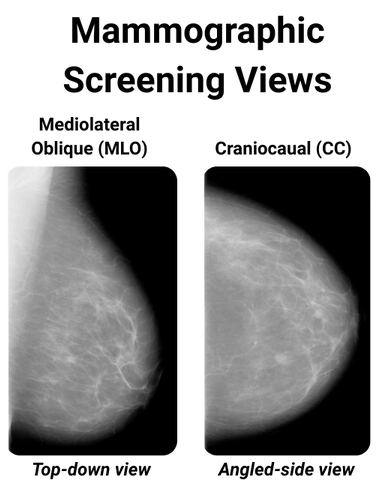

X-ray Mammography is a breast cancer screening method and remains one of the more effective population-wide tools for early detection of Breast Cancer 1. The breast is compressed between two plates to spread the tissue and reduce motion blur evenly. A typical screening exam records two views of the breast: Caniocaudal (CC), a top-to-bottom view, and Mediolateral (MLO), a side view.